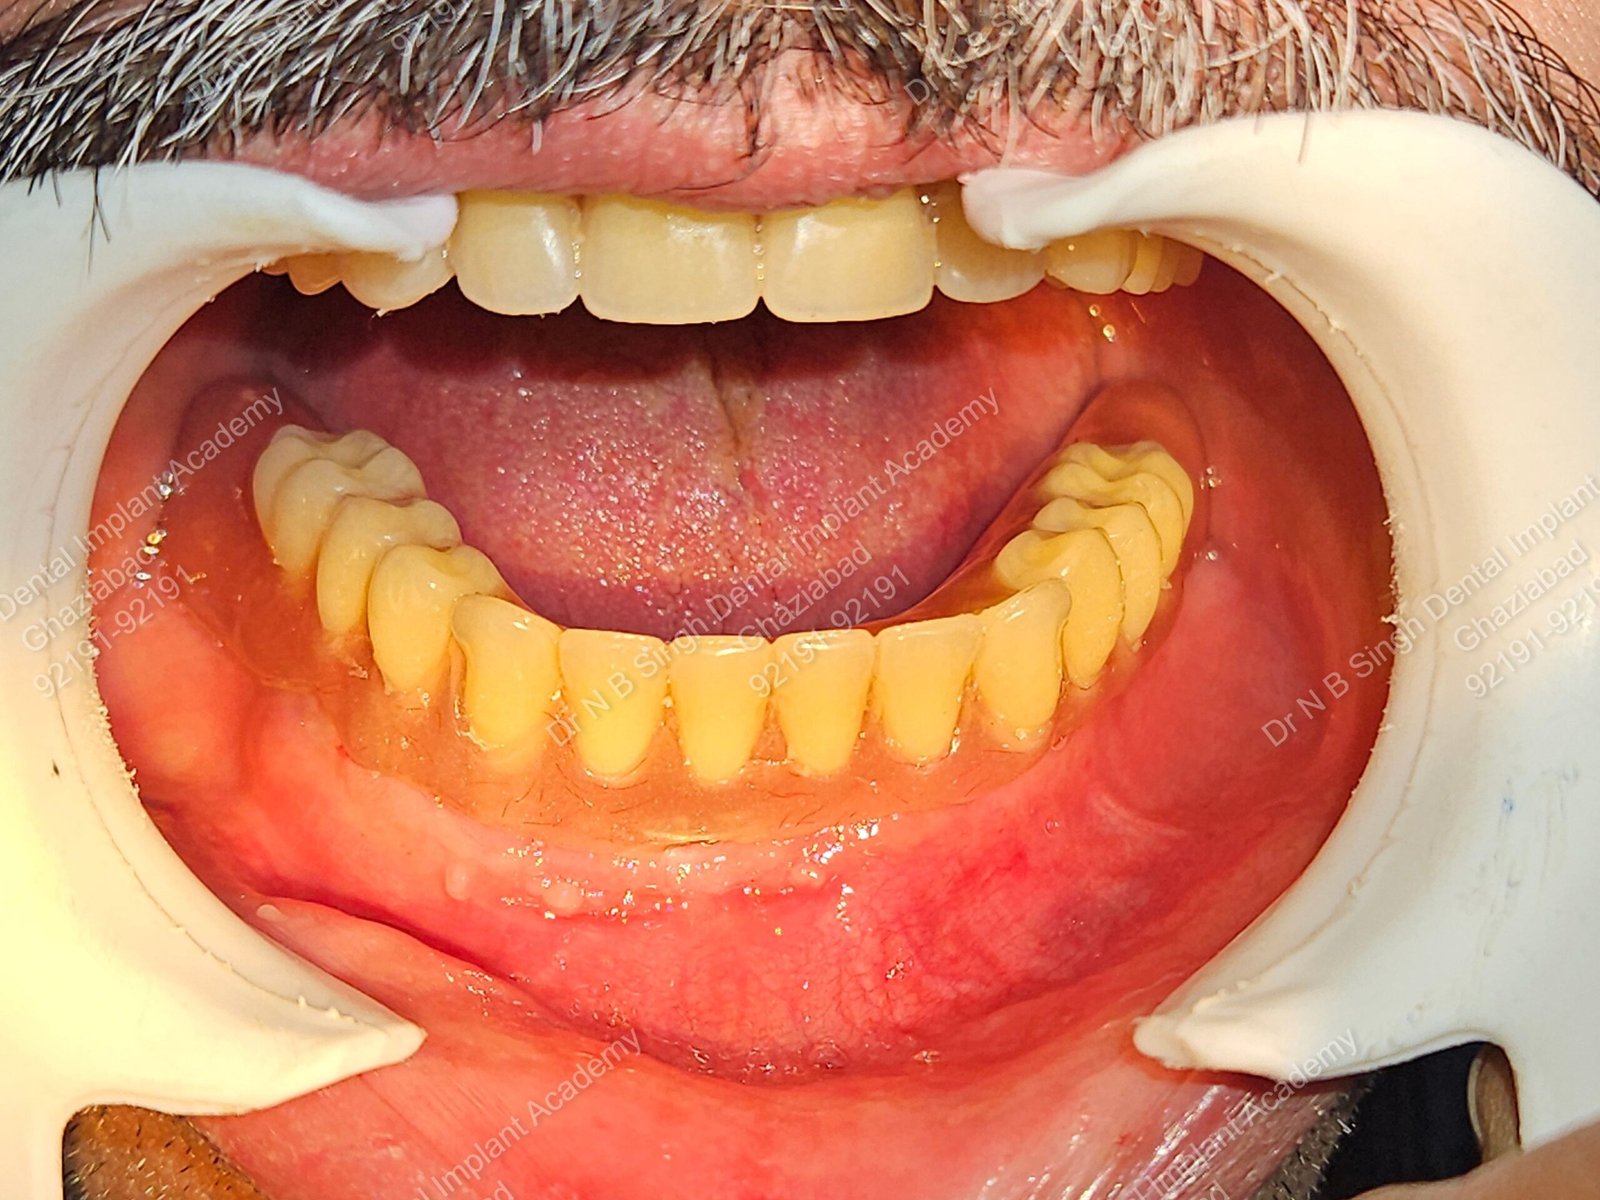

1006 Basal implant full mouth-DEEPAK

1006 -29

1006 -28